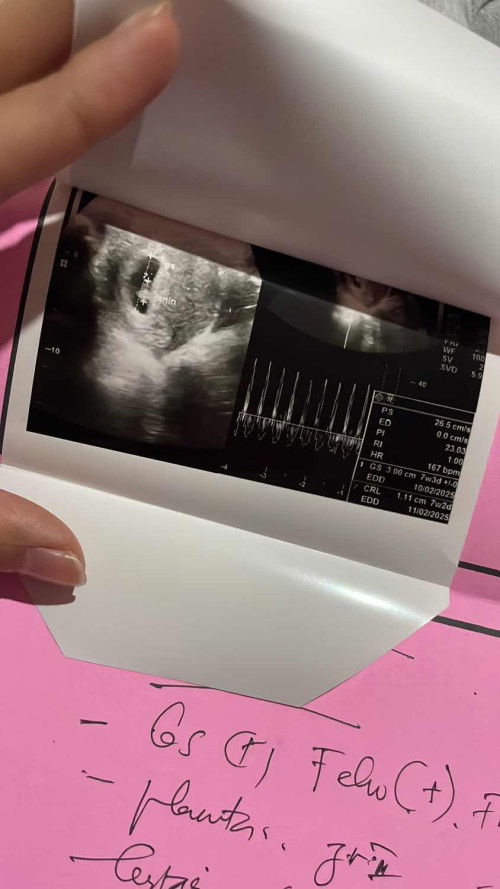

Dari seminggu lalu demam naik turun. Lalu hari ke5 otw rumah sakit karna benar2 demam sampe 40 dan itu berulang2 sampai aku flek beberapa waktu. Setelah dicek darah rutin berhari2 ternyata aku positif dbd. Ga nyangka tapi saat ini trombosit perlahan kembali normal. Dan ini usg di 8week udh lengkap semua, kantung, plasenta juga djj puji Tuhan semua bagus dan sehat. Semoga semakin kuat untuk menjalani kehamilan ini.. #bantusharing #sharingcaring #secondborn